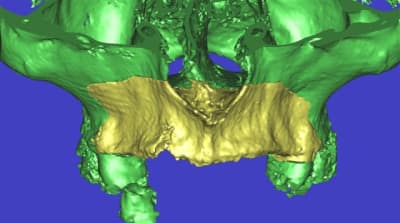

L’idée de base est d’obtenir un greffon adapté à la zone à greffer, et de donner plus de chance à la nature de faire son travail de reconstruction.

Une fois les greffons préparés, ils sont traités par un procédé spécifique à Biobank (CO2 supercritique) puis stérilisation (rayons gamma), et vous le verrez la pose devrait être extrêmement simplifiée.

La première diapo est un essai pour justifier le concept (os non destiné à une utilisation greffe)

la deuxième est "tapée" dans une tête de femur de mauvais qualité (rejetée)

la troisième et suivante ce sont "les greffons" définitifs.

concept très prometteur. on obtient effectivement un contact intime du greffon avec le site receveur.

Pour la mise en forme de la pièce 1 (appui 12) avec la mise en place, le choix de la tête de fémur, et les discussions pour expliquer la mise en forme, il a fallu 1 h environ, qui pourrait etre réduite à une trentaine de minutes, dans un cas comme celui ci, ce qui est déjà énorme pour l'os d'un patient (mise à nu ect...), sans parler des différents stress.